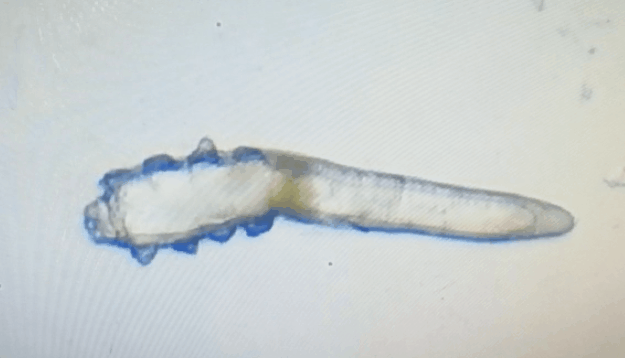

32歲的陳先生在一家互聯(lián)網(wǎng)公司上班,除了工作,陳先生還喜歡逗養(yǎng)寵物,常年和金毛形影不離。幾天前,陳先生的眼睛奇癢難耐,一揉眼睛,睫毛就會大量脫落,無奈下,陳先生到附近的廈門眼科中心干眼中心檢查,竟發(fā)現(xiàn)睫毛上布滿了大小不一的蟲子在蠕動。經(jīng)診斷,陳先生的眼睛不僅出現(xiàn)瞼緣炎,還伴有干眼癥。通過OPT激光、除螨濕巾、熏蒸SPA等聯(lián)合治療,陳先生的眼睛重獲健康。

林女士是一家公司的白領(lǐng),常常需要濃妝出席各種會議,然而光鮮亮麗的背后,林女士的眼睛正遭受著和陳先生同樣的癥狀。在螨蟲鏡檢中,當(dāng)看到自己的睫毛上爬滿了十幾只透明的生物-螨蟲,林女士嚇了一跳。幸而,經(jīng)過廈門眼科中心干眼中心的治療,林女士解決了多年的眼睛干癢問題。

這就不得不提到眼科醫(yī)生經(jīng)常使用的螨蟲檢測工具——螨蟲鏡檢。它通過顯微利器,無死角全方位掃描你的睫毛,讓螨蟲無處遁形。